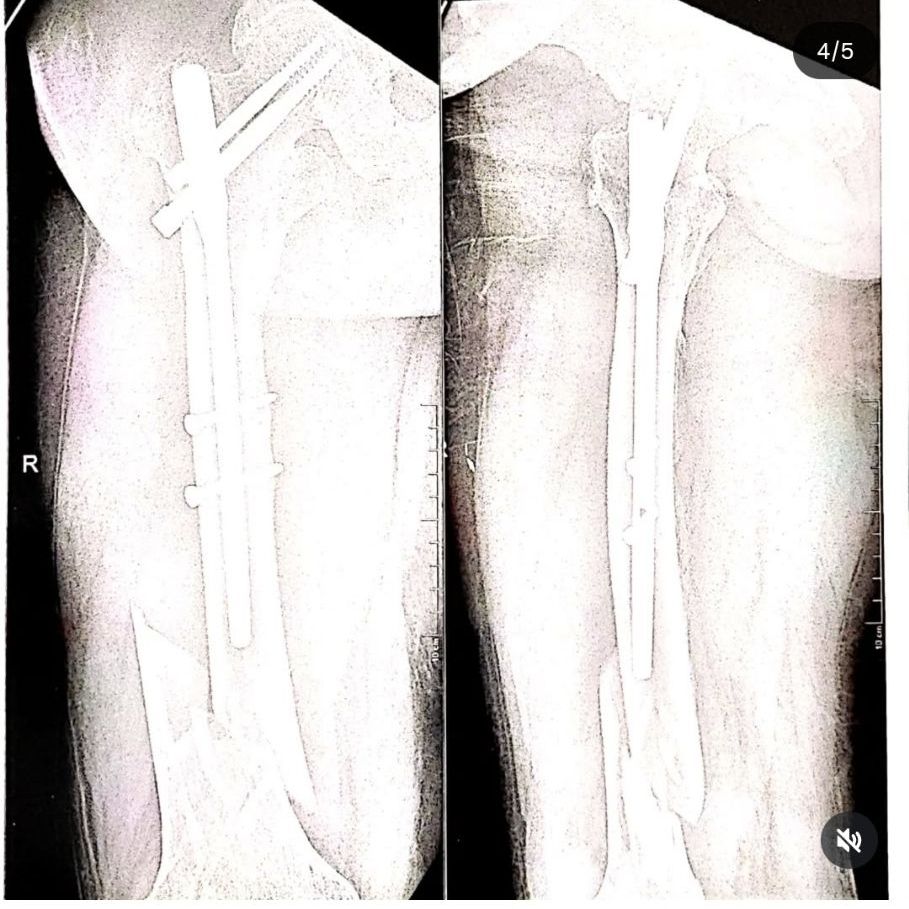

It was so so heartbreaking to know. He sounded in so much pain. He had his surgery the next day and we met him yesterday. He’s still in a lot of pain. Has screws and plates inserted in his leg and it’s going to be a while before he is back. Even in the pain he asked about the “bacchas” and said he dreamt of one of them looking for him 凉梁…

The bill is attached in a slide here ..they were covered 60% by insurance and have paid the rest from their pocket.

The total bill was 3,09,774!!! (Attached here)